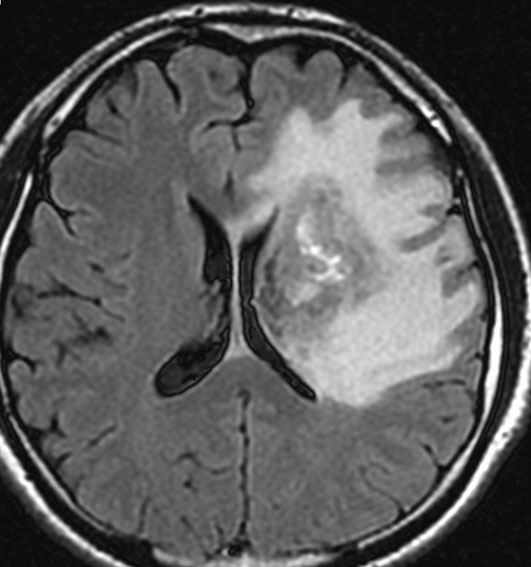

アバスチン投与後15日目

たった2週間で劇的な改善が見られました。失語症と片麻痺や認知機能も改善しました。

4回目のアバスチン投与後

アバスチンをどれだけ続ければいいのかははっきりしていません。2週間おきに6コースまでの投与が基本かもしれません。

この画像を見ると,放射線とテモダールの治療が有効であったのかなと思います。